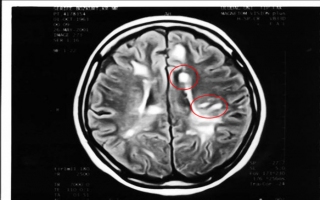

FELÇ (Stroke-İnme-Serebrovasküler olay) Beyin felci genelde 2 şekilde olur. 1-Damar tıkanıklığı 2 ...

MS - MULTİPLE SKLEROZ - PLAK HASTALIĞI Bu hastalıkta beyinde sinirlerin etrafındaki yağ ( miyelin ) ...

EPİLEPSİ - Beyinde oluşan anormal aşırı elektrik aktivitesi sonucu meydana gelir. Sonuçta beyinde b ...